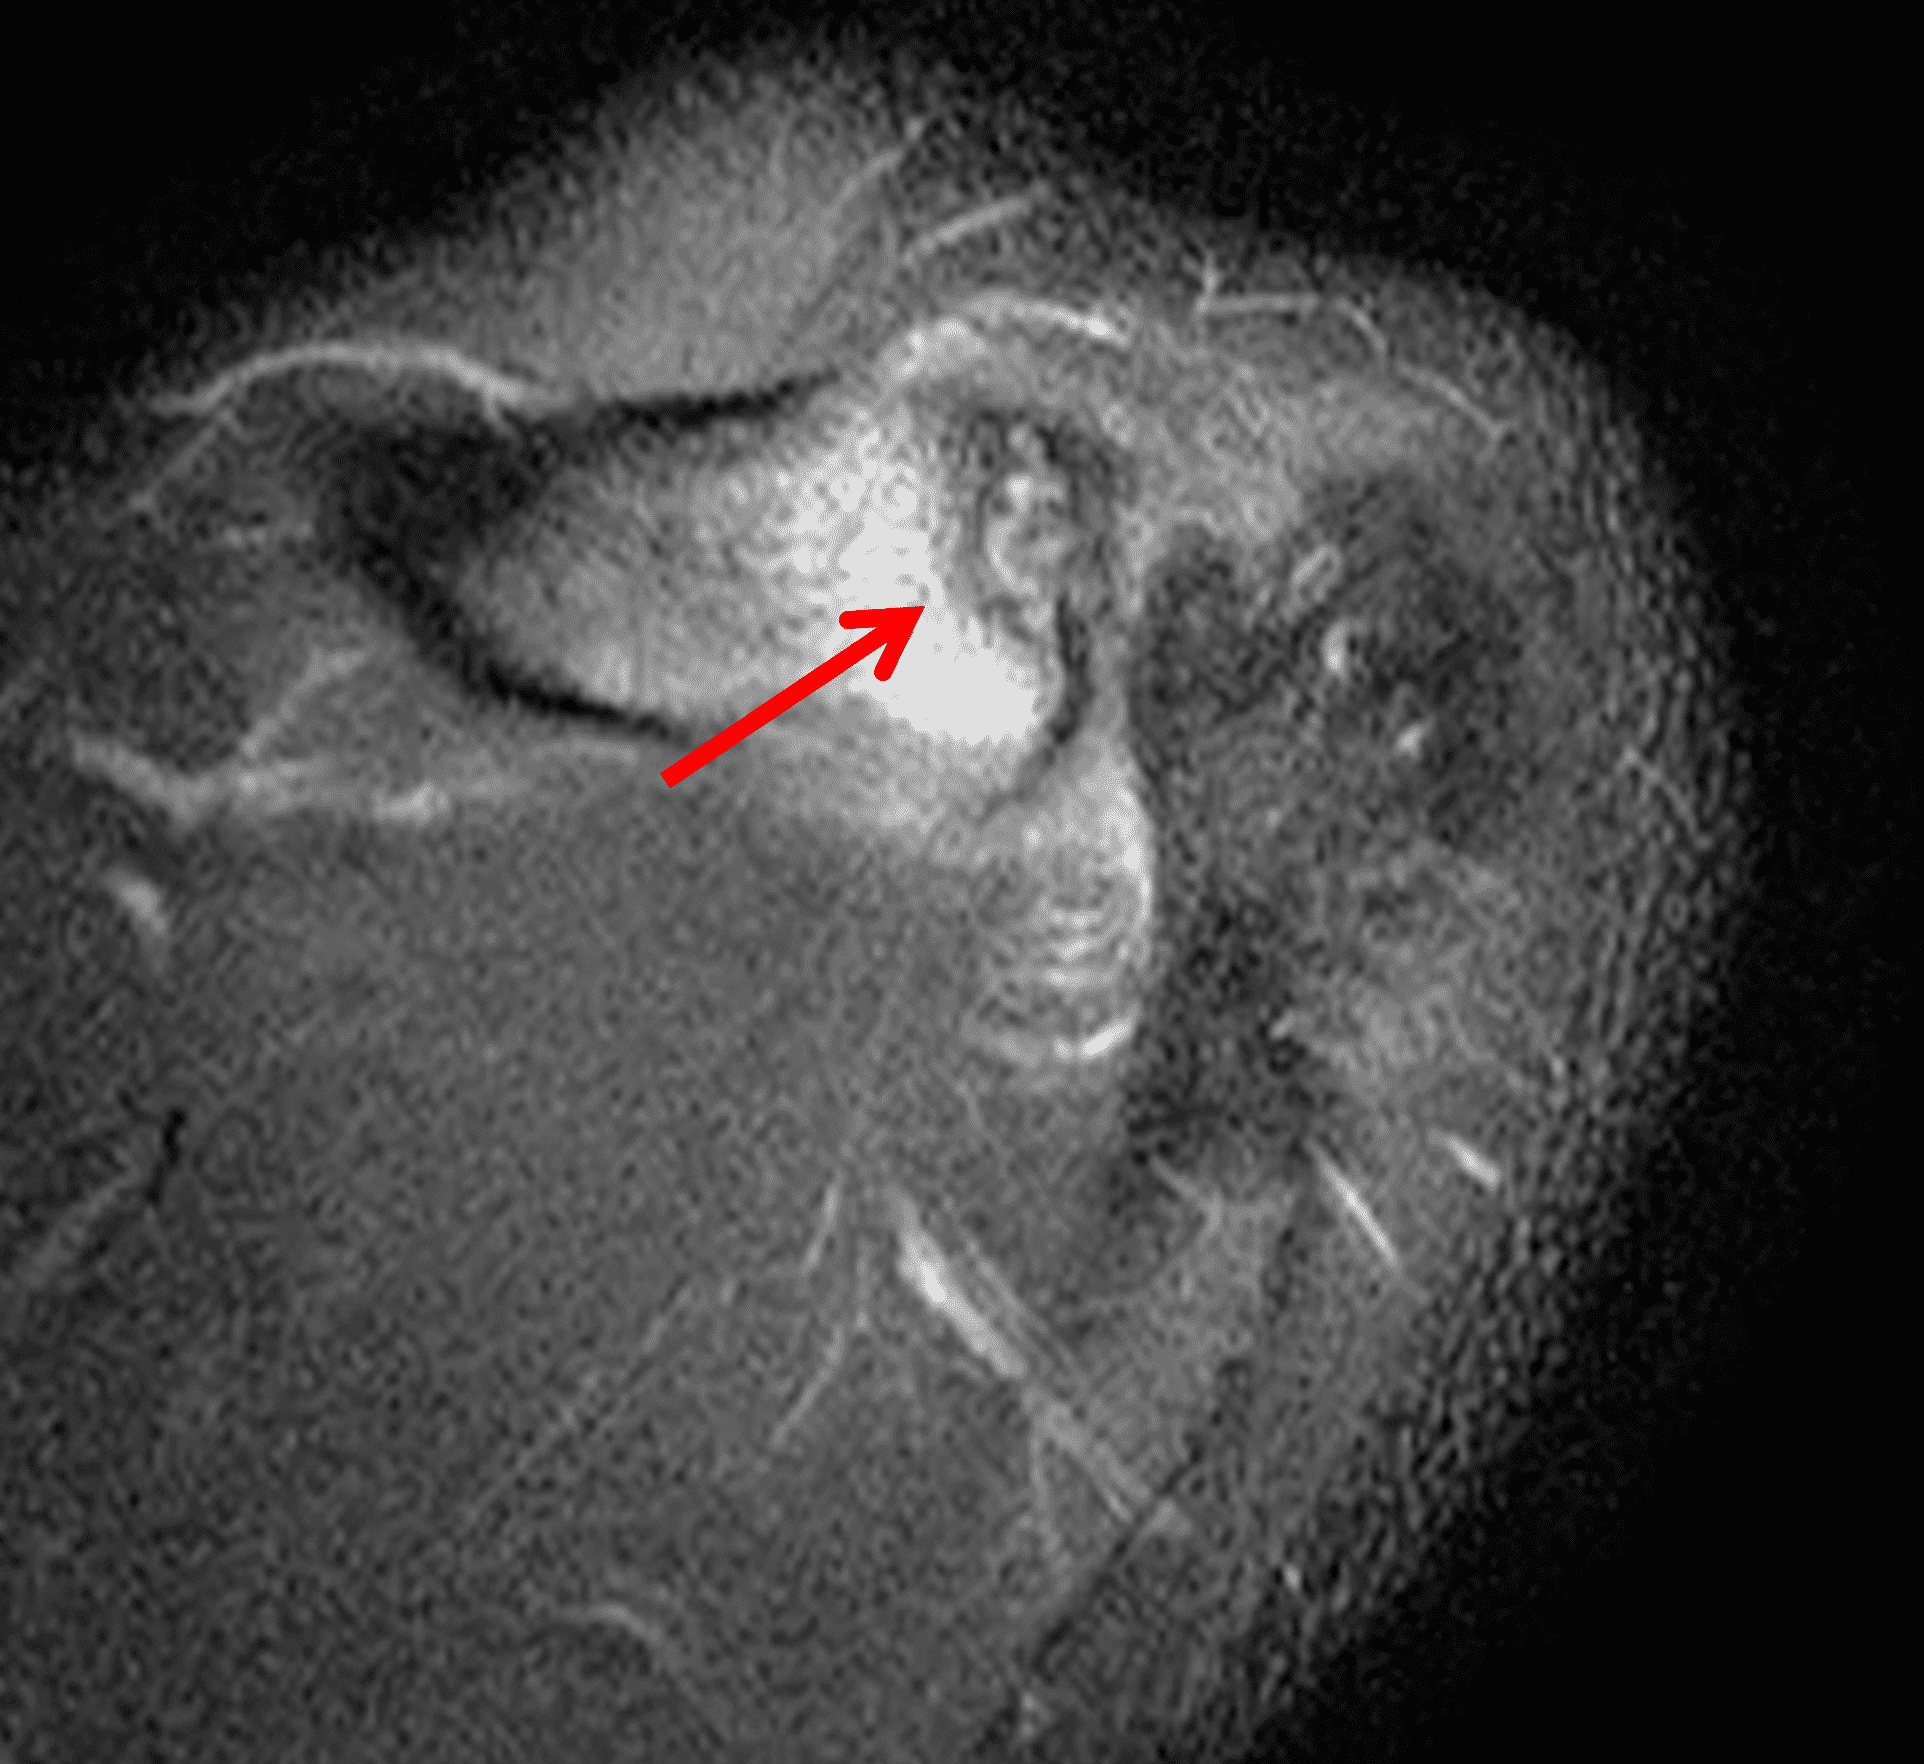

A 49-year-old male, avid weightlifter complains of chronic pain along the superior aspect of his right shoulder. He denies acute trauma. An AP radiograph (Figure 1A), as well as oblique coronal SPAIR (Figure 1B), axial fat-suppressed fluid sensitive (Figure 1C), and oblique sagittal T2-weighted images (Figure 1D) are shown. What are the findings? What is your diagnosis?

MRI: MRI is the primary imaging modality used for the diagnosis of DCO and identifies relevant findings earlier than radiographs or CT.  To differentiate DCO from similar conditions, it is important to identify underlying findings that are isolated to or more pronounced in the distal clavicle compared to other structures.  Osseous changes along both the acromial and distal clavicular margins of the joint often point to a different diagnosis.2

The principle MRI finding of DCO is distal clavicular marrow edema and surrounding inflammation on fluid-sensitive pulse sequences, especially with fat suppression (Figures 3 and 4).2, 9 Marrow changes can occur in patients with normal radiographs,10 in which case a term like “stress/overuse related marrow edema,” might be preferable to “osteolysis.” On MRI, more severe cases may show erosions or cysts in the distal clavicle and loss of the subchondral bone plate in addition to more pronounced marrow and soft tissue edema. A band of low signal paralleling the distal bone end may be present, suggesting a stress fracture line (Figure 5).8 However, a similar appearance can be due to the sclerotic rim surrounding distal clavicle cysts or small erosions (Figure 6). A small effusion or mild synovitis is often present in the AC joint.  Soft tissue edema within and surrounding the AC joint capsule and distal clavicular periosteum may be visible (Figure 3).  Some patients may also show marrow edema (or even erosions) in the anterior acromion, but the changes are typically more severe in the distal clavicle (Figures 5 and 7).2